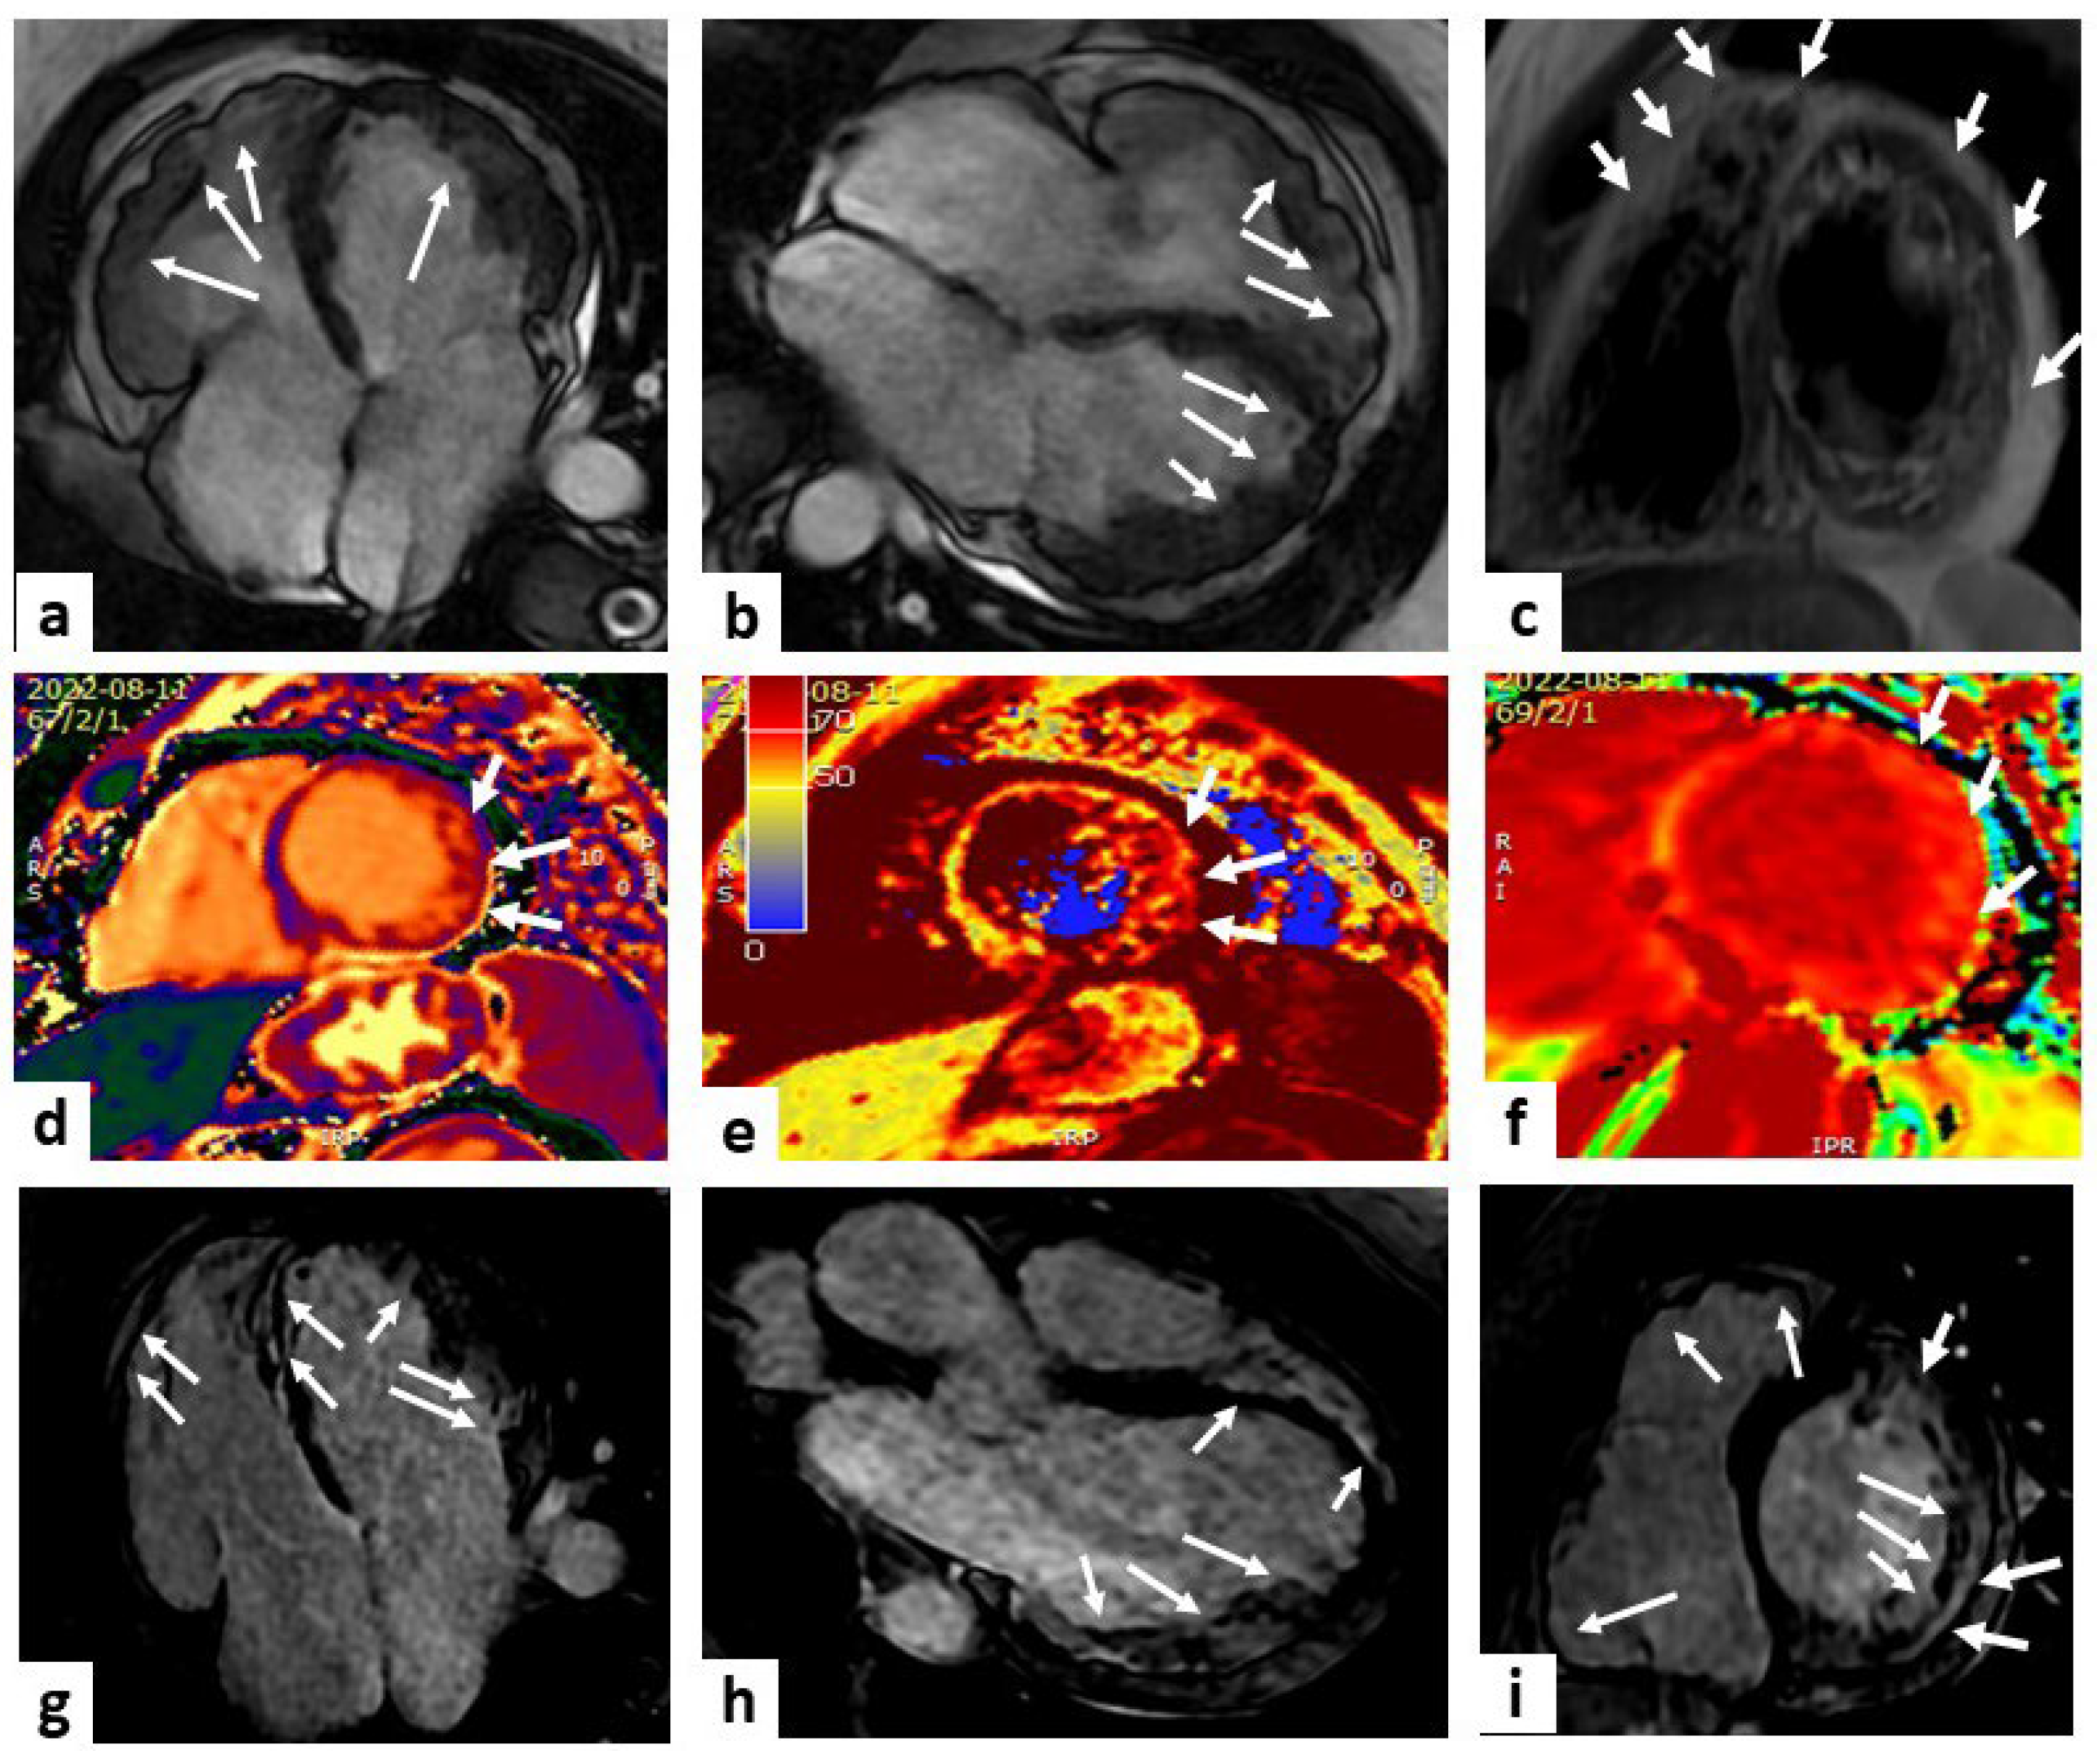

The presence and extension of fibro-fatty myocardial replacement (ARVC pathologic hallmark) can be detected using LGE imaging and is found in up to 88% of patients, with a diagnostic accuracy of 98% when wall motion alterations and pre-/post-contrast signal abnormalities were considered together [78,79,80], although LGE can be detected in other conditions (e.g., sarcoidosis, rheumatic disease, myocarditis), and its interpretation can be difficult due to RV limited thickness [81] (Figure 4).

Figure 4.

Arrhythmogenic right ventricular cardiomyopathy. A case of a 50-year-old female with a history of premature ventricular beats. Cardiac magnetic resonance (CMR) imaging showed multiple bulging of both LV and RV ventricles (white arrowheads) in steady-state free precession (SSFP) sequences (panels (a,b) show 2 slightly different four-chamber views). Possible fat infiltration of posterolateral wall emerged by proton density (PD) sequences (white arrows in panel (c) displaying a mid-LV short-axis view). Panels (d–f) show short-axis views of the mid-LV at T1 and T2 mapping and ECV, respectively, with evidence of a higher value at the level of the lateral wall compared to the remaining myocardium (white arrows). Late gadolinium enhancement (LGE) sequences displayed a non-ischemic hyper-enhancement pattern (white arrows) at the level of the septum, LV, and RV multiple positions (panels (g–i) show four-chamber, three-chamber, and mid-LV short-axis views, respectively). These findings are diagnostic for biventricular arrhythmogenic cardiomyopathy.

More controversial is the role of CMR mapping as a tool for ARVC diagnosis and risk stratification. CMR mapping, recognizing areas of fibrofatty replacement in the RV, can be useful for discovering early stage disease and guide patient management [82]. In the study by Bourfiss et al., patients with genotype-positive ARVC and their at-risk family members have higher native T1 values compared to controls [83].